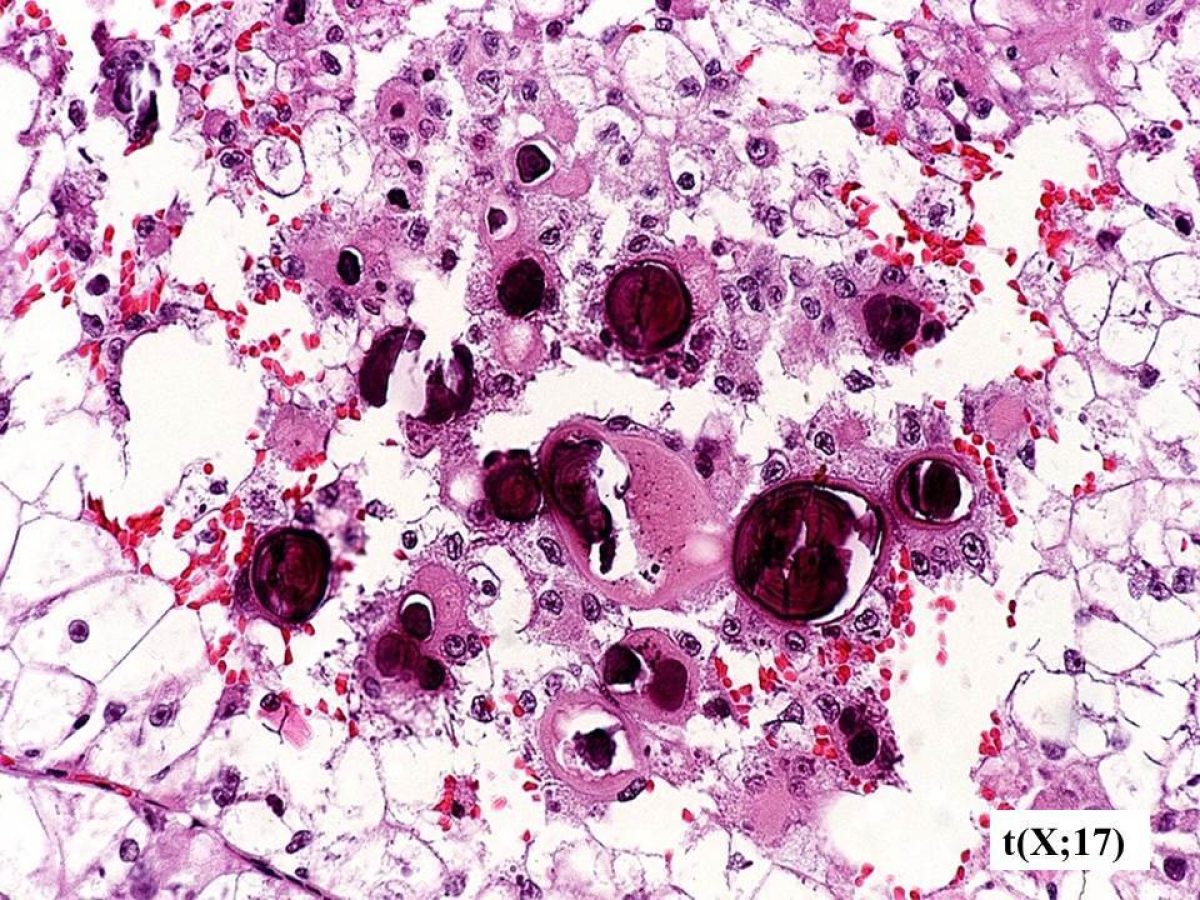

These pathology images are examples of what Translocation Renal Cell Carcinomas look like under the microscope.